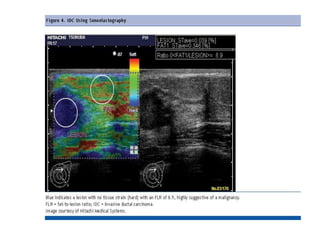

Elastography

• Elastography is a newer technique that

exploits the fact that a pathological process

alters the elastic properties of the involved

tissue. This change in elasticity is detected and

imaged using elastography.

• Elastography is a non invasive imaging which is

based on the principle - when a mechanical

compression or vibration ( stress ) is applied, the

tumor deforms ( strain ) less than the

surrounding tissue.